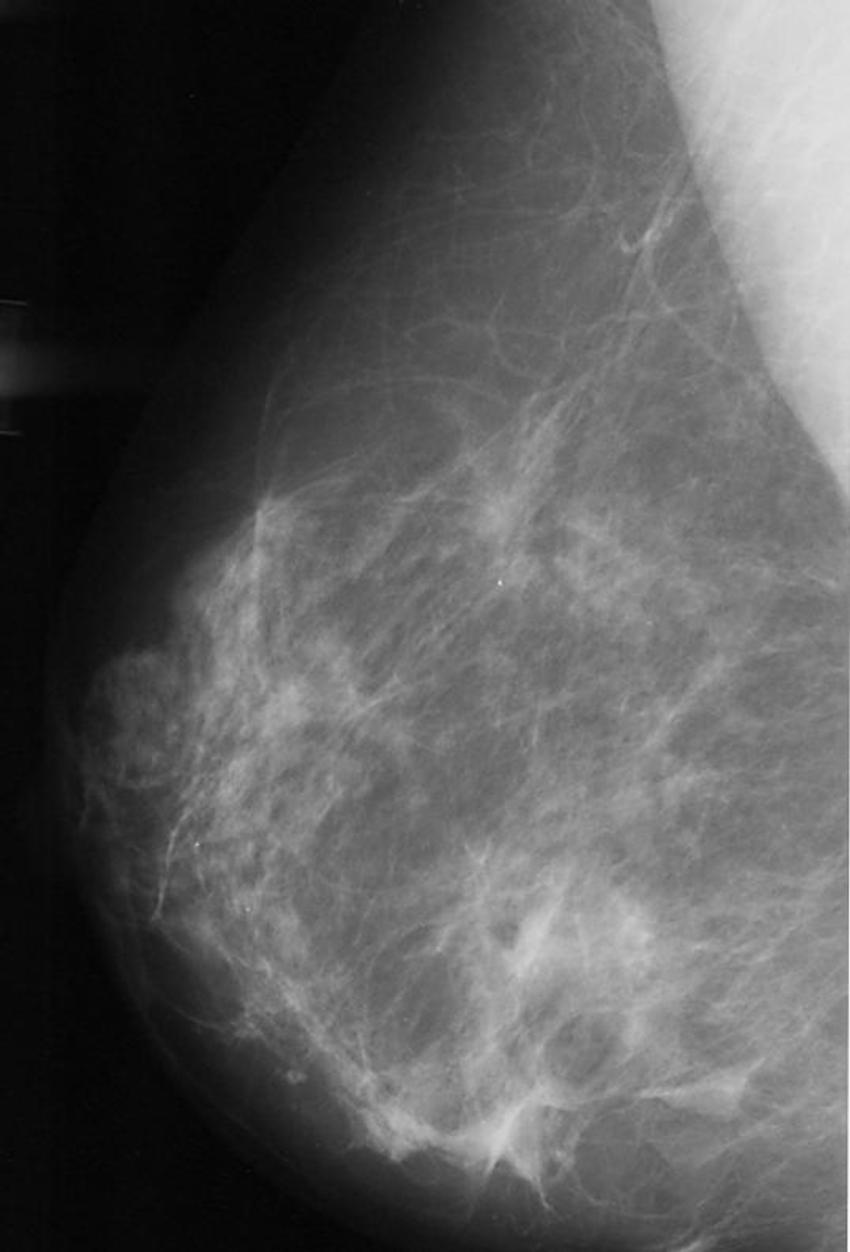

Figure 1. Abnormal mammogram.

Figure 2. Normal mammogram.